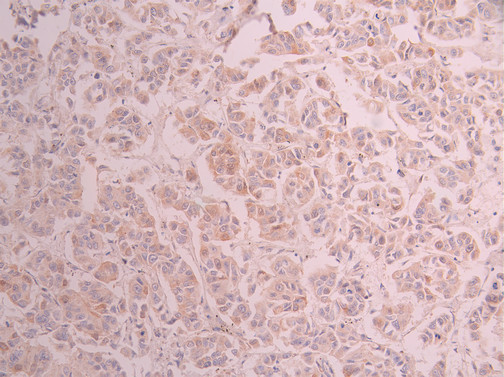

IHC image of CSB-RA961114A0HU diluted at 1:100 and staining in paraffin-embedded human kidney tissue performed on a Leica BondTM system. After dewaxing and hydration, antigen retrieval was mediated by high pressure in a citrate buffer (pH 6.0). Section was blocked with 10% normal goat serum 30min at RT. Then primary antibody (1% BSA) was incubated at 4°C overnight. The primary is detected by a Goat anti-rabbit polymer IgG labeled by HRP and visualized using 0.05% DAB.